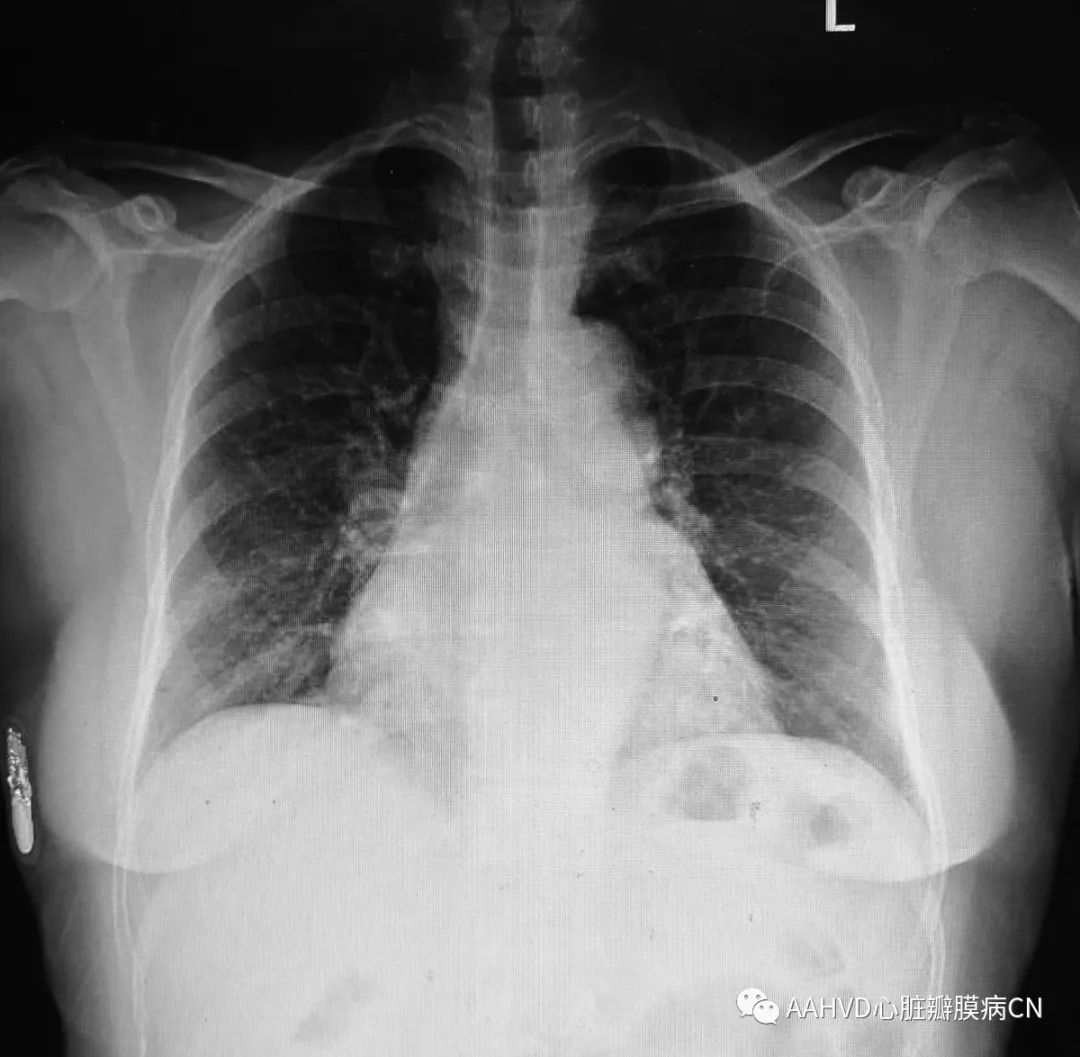

术前胸片

640_6

术前经胸超声:

风湿性心脏病,二尖瓣返流面积14.1cm²(重度返流),瓣口面积1.4cm²(重度狭窄),前向流速196cm/s,三尖瓣返流面积8.1cm²(中度返流)。室间隔基底段增厚(12cm)。